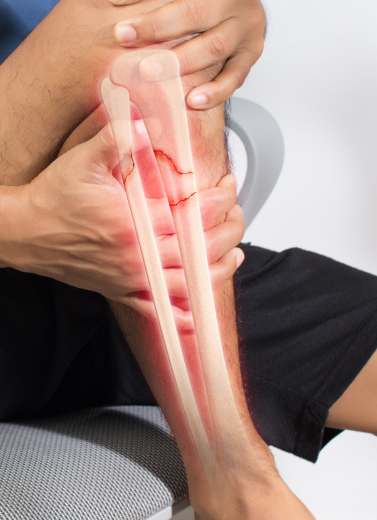

We Treat All Types of Bone Injuries and Trauma Cases

Complex & Comminuted Fractures

Non-Union or Delayed Healing Fractures

Proper alignment = proper healing

Reduced risk of long-term disability

Minimally invasive options when possible